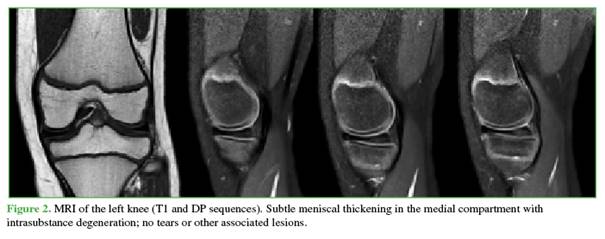

He was referred to an orthopedic subspecialist. Physical examination revealed tenderness on palpation of the medial joint line, painful flexion-extension with full range of motion (0-130°), and a positive medial McMurray test; the remainder of the exam was normal. Given these findings, an MRI of the left knee was requested (Figure 2). Imaging showed an enlarged medial meniscus (incomplete) without displacement, with intrameniscal degeneration.